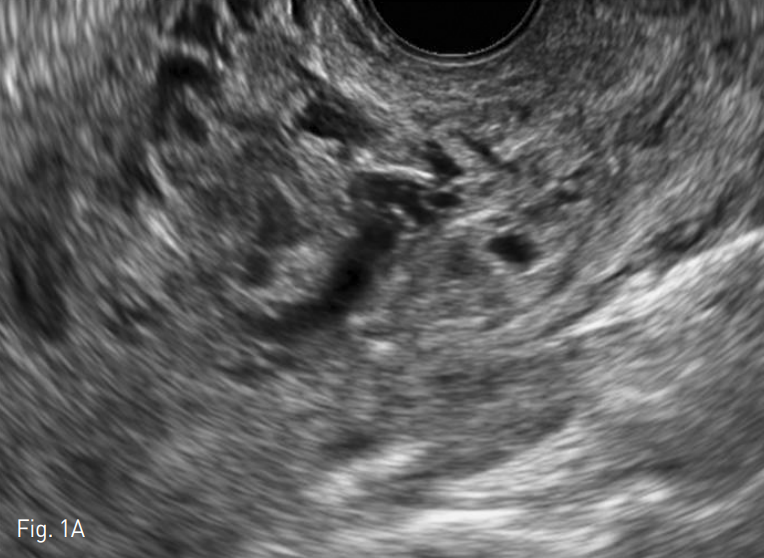

질식 초음파상에서 자궁에 큰 혈관성 종괴가 발견되었다. 종괴 내부에는 무에코성의 불규칙적인 관상 구조물이 관찰되었는데 이들은 색도플러 초음파에서 여러 방향의 빠른 속도를 보이는 동맥혈류를 가진 혈관 덩어리였다 (Fig. 1). 이후 복부전산화 단층촬영을 시행하였고, 자궁의 앞쪽 벽과 자궁강을 침범하는 장경 8cm 크기의 종괴를 확인할 수 있었다. 종괴 내부에는 비정상적인 혈관으로 보이는 구불구불한 관상의 조영증강 구조물들이 있었고, 자궁주변에 동맥기에서 조기 조영증강을 보이면서 비정상적으로 비대해져 있는 정맥도 관찰되었다 (Fig. 2).

Fig. 1

A. Gray scale transvaginal US shows a large intramyometrial mass with anechoic structures.